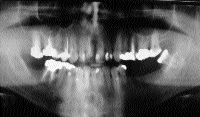

FIGURE 12

Several years ago I sat and listened intently at a meeting of the American Academy of Craniofacial Pain (formerly the Academy of Head, Neck and Facial Pain) as Dr. Clifton Simmons described how he injected the TM joint to unlock a non-reducing disc displacement (NRDD). Prior to this, I was sending patients with NRDDs to … Read more